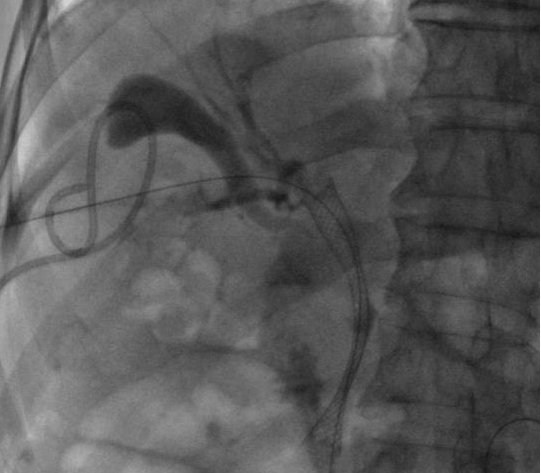

ERCP(內鏡逆行胰膽管造影術)是膽胰疾病精準內鏡診療技術,具有不開腹、風險小、創傷小、恢復快、住院時間大大縮短的優點,尤其是對年齡大、體弱多病的患者尤為適宜。ERCP主要運用于膽總管結石的取出,以及在經口膽道子鏡的輔助下完成肝內膽管結石的取出。

ERCP取出膽總管結石

對于無法手術切除的膽管或胰腺惡性腫瘤導致的梗阻性黃疸,可以進行ERCP下膽道支架植入,以緩解梗阻性黃疸癥狀,提高患者生活質量。通過光動力、射頻消融等治療,還可以控制腫瘤的生長,提高膽道支架的通暢期,延長患者生存時間。

膽道惡性梗阻膽道支架置入